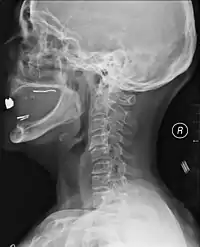

Рентгенографічна оцінка за допомогою рентгенографії, КТ або МРТ може визначити, чи є пошкодження хребта й де вони локалізуються. Найбільш доступними зазвичай є рентгенівські знімки [73] , які можуть виявити нестабільність або нерівність спинного стовпа, але не дають дуже детальних зображень і можуть пропустити травми спинного мозку або зміщення зв'язок або дисків. Таким чином, коли результати рентгенографії є нормальними, але спинальну травму все ще підозрюють через біль або симптоми випадіння чутливості чи рухів, використовують КТ або МРТ. [73] КТ дає більше деталей, ніж звичайна рентгенографія, але більше опромінює пацієнта [74], й до того ж, усе ще не дає зображень спинного мозку й міжхребцевих зв'язок. МРТ найбільш детально показує структури тіла і є стандартом при виявленому неврологічному дефіциті. [75]